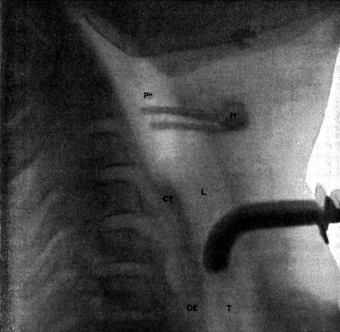

| 334. | Radiograph to show the Value of the Röntgen Rays | 639 |

| 335. | Radiograph showing Canula in the Frontal Sinus | 639 |